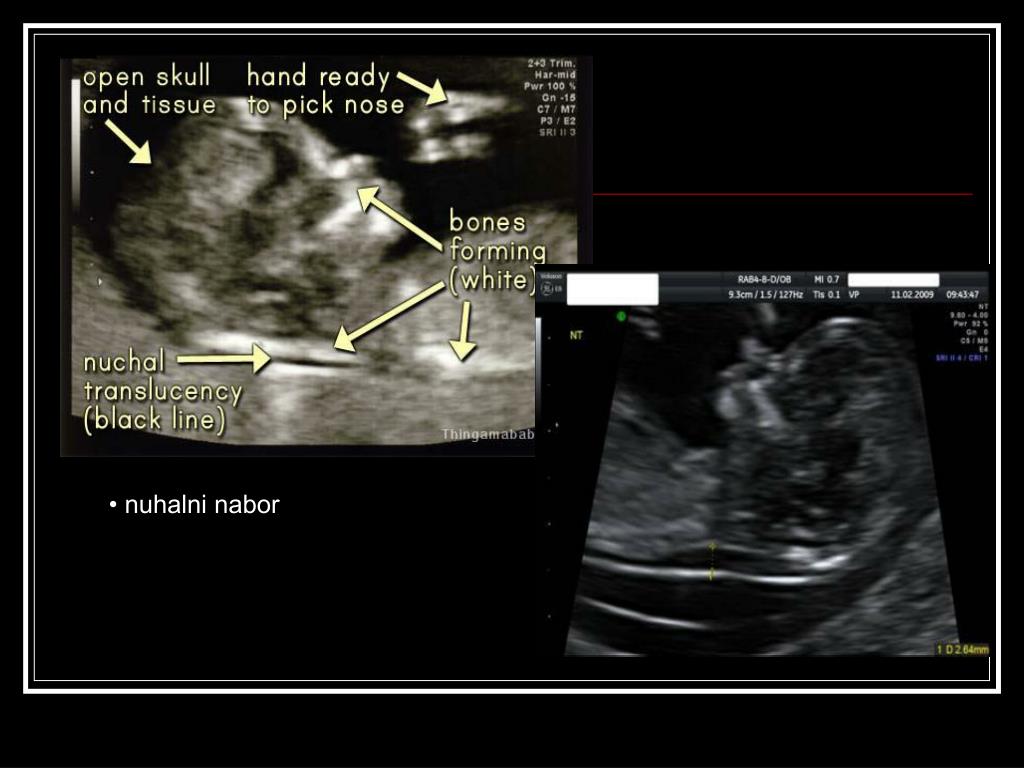

22. • nuhalni nabor

21. UZV biljezi kromosomopatija I tromjesečja:Nuhalno prosvjetljenje • prekomjerno nakupljanje tekućine u potkožnom tkivu nuhalne regije; poremećaj drenaže limfne tekućine ili srčana kongestija • UZV: mjeri se najšire područje hipoehogene nuhalne nakupine tekućine u mediosagitalnom prikazu- granična vrijednost između 10-14tj je 2.5- 3mm Moguće etiologije nastanka: - promijenjen sastav kolagena (Downov sindrom) - abnormalna nuhalna limfogeneza (Turnerov sindrom) - hemodinamske promijene i srčana dekompenzacija